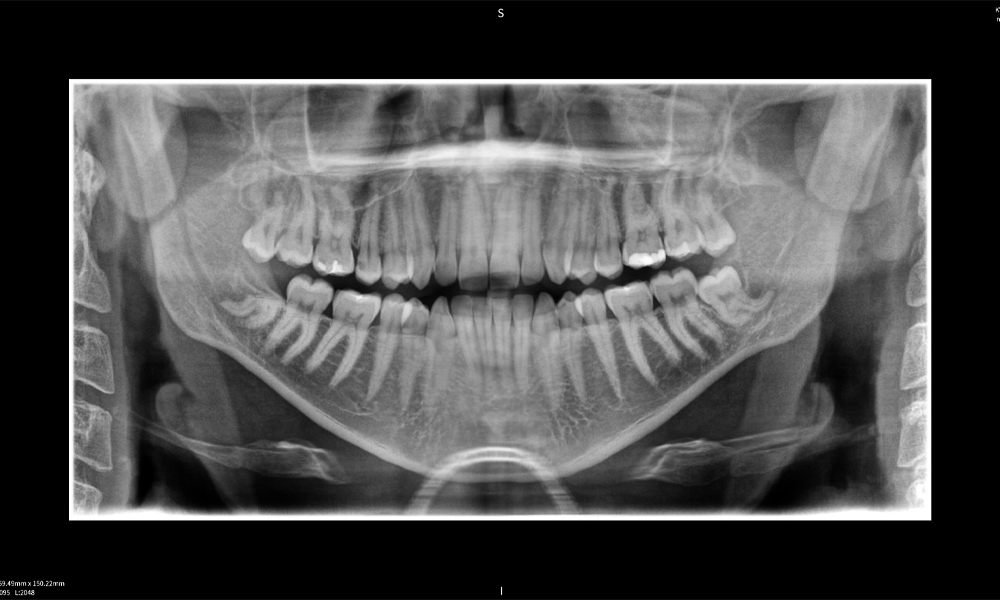

Figure c: Imaging results of Seethrough Max, in front of a black background.

Figure c

Figure e: The panoramic X-ray serves as an initial assessment tool, showing the general positioning of the teeth as well as any potential pathological changes. Notably, on the right side (tooth 48), the situation following a crown amputation performed by an external practitioner is visible. The two severely curved roots remain in close topographical proximity to the inferior alveolar nerve within the bone. This suggests a deliberate decision to avoid the increased risk of nerve injury during a complete extraction, and represents a clinically relevant finding. In summary, CBCT scans with Seethrough Max, provide crucial information about the complex anatomy and the critical relationship between the wisdom teeth and the inferior alveolar nerve. This detailed preoperative diagnostic imaging is essential for safe and successful surgical procedures in the mandibular region.